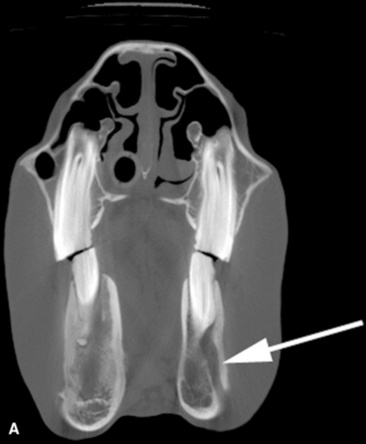

The horse is anisognathic, which means that the bottom jaw is narrower (by about 25%) than the upper jaw. The molar tables are sloped at a 10- to 15-degree angle from dorsal lingual to buccal ventral (Fig. 32-16). Lateral excursion of the jaw during mastication favors occlusal wear of the buccal aspect of the lower molar arcades and the lingual aspect of the upper molar arcades. As the horse chews, the jaw moves in a rotary motion from side to side with limited rostral to caudal excursion. The molars are constructed so that the enamel, cementum, and dentine interdigitate to provide a sharp, serrating surface that allows for uneven, continuous wear when the horse is eating.

image

Fig. 32-16 Computed tomographic scan of the equine skull at the level of the first molars. Dorsal is at the top. Note that because the upper molars are offset laterally from the lower molars, the molar tables are sloped at a 10- to 15-degree angle from dorsal lingual to buccal ventral.